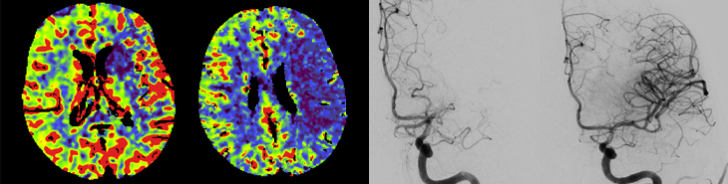

Diagnostically and therapeutically, the most modern methods and equipment are available for our patients. In addition to diagnostic neuroradiology, our clinic is characterized by a high level of expertise in minimally invasive neuroradiological therapy, both in the emergency treatment of strokes and in the elective treatment of aneurysms, vascular stenoses and vascular malformations.